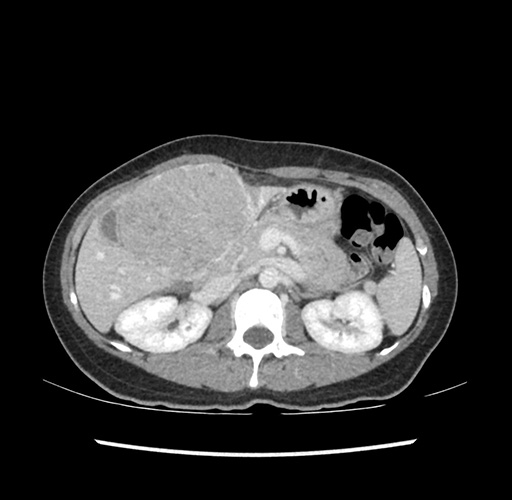

Imaging Analysis

Look through the patient's CT scan to identify any areas of concern for the necessary procedure.

Based on your CT findings, which issue(s) would give reason for "planned slowing down moment(s)" in this case?